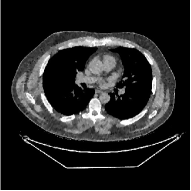

This paper was inspired by a simple observation related to our recent study [34]: for the penalized weighted-least squares (PWLS) reconstruction method using prior with a learned ST (PWLS-ST-) [34], the sparsification error histograms match a Laplace distribution over the iterations; see Fig. 1. The question then arises, “Does the learned prior experience model mismatch in testing stage?” To answer this question, we aim to investigate learned STs for regularization. This paper

The term denotes a -based sparsification error [3, 4, 5]. We expect to be more robust to sparsity model mismatch than the -based sparsification error used in [34, 36]. Fig. 1 shows histograms of sparsification error at different outer iterations of the PWLS-ST- method. Over the iterations, the sparsification error histograms appear more like a Laplace distribution than a Gaussian distribution. This observation suggests that the proposed prior model is more suitable than the prior model for PWLS-ST-based reconstruction. Section III-B1 shows that the proposed -based sparsification error term, , improves the accuracy of reconstruction compared to the prior model in [34, 36].